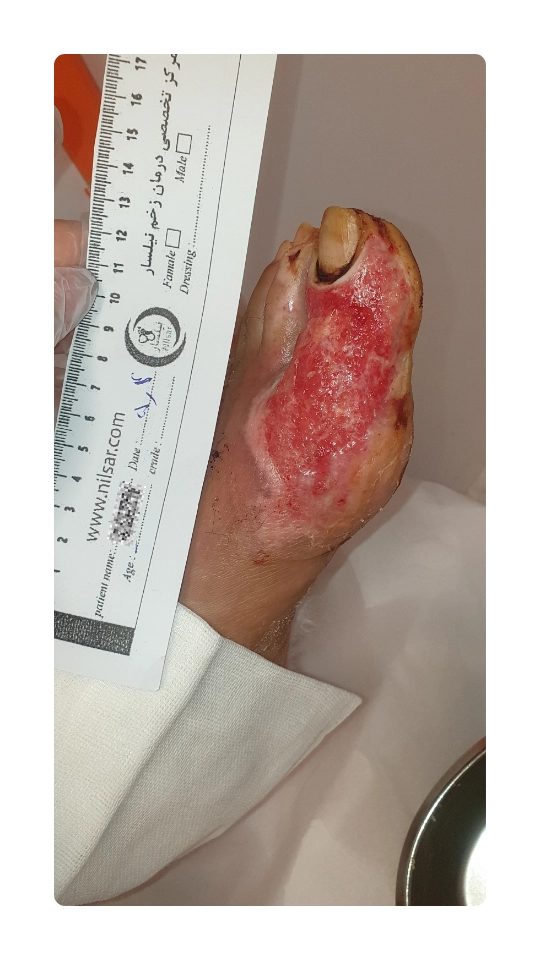

نمونه درمان زخم سوختگی در بیمار دیابتی

سوختگی